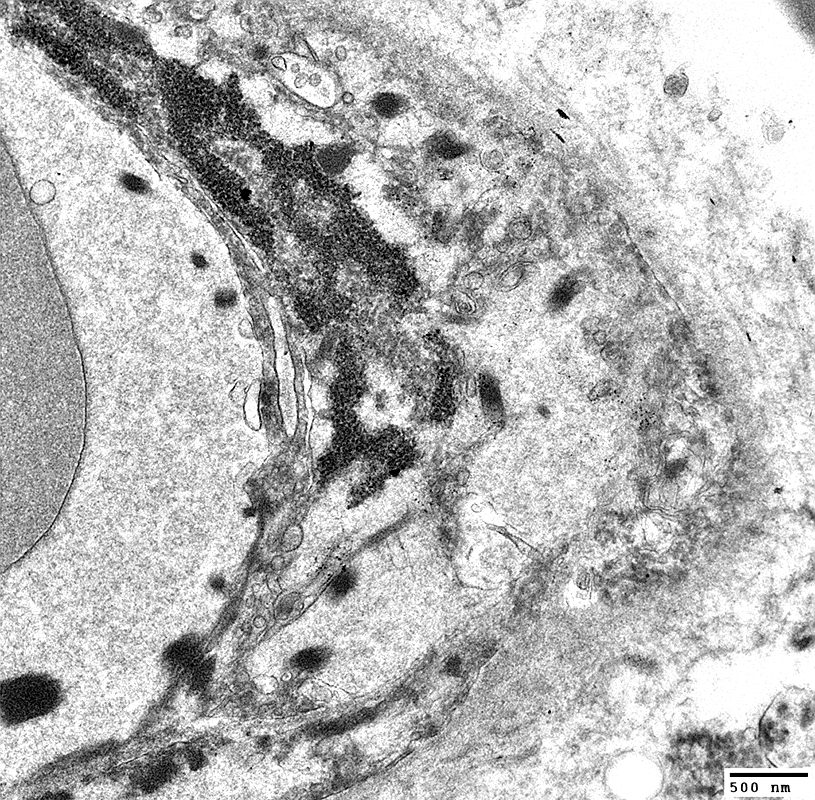

MELAS: Mitochondrial Ultrastructure

From: R Schmidt

Pericytes   Mitochondrial proliferation & enlargement (Black arrows)

Endothelial cells   Multiple small vacuoles (White arrows)